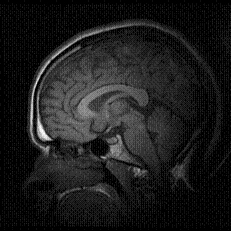

The major organs have relatively simple, specialist

functions, ergo; the genetic engineering of

these organs is relatively simple. It is when

we get on to the brain and intelligence that

the story gets a little more complex.

Researchers

believe they have begun to identify the genes

that give us our intelligence. However, there

is a huge debate about how much 'intelligence'

is derived from genes and how much from environmental

influences. The jury is still out on whether

our cognitive abilities are purely genetic,

the most likely scenario is that it is a combination

of factors that give us our 'intelligence'.